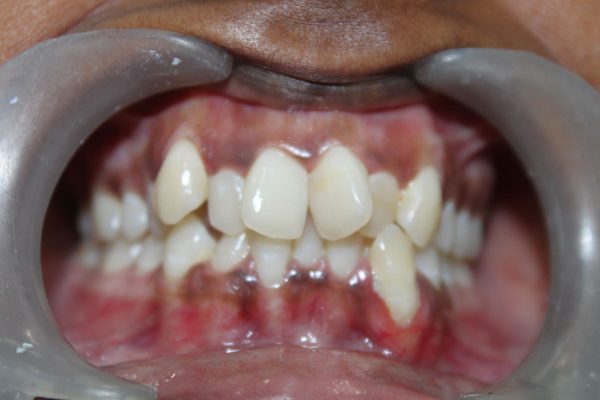

You may have heard crowded teeth referred to as dental crowding or overcrowding. This happens when your mouth does not have enough space for your teeth to grown in properly. This is a type of malocclusion resulting in overlapping and crooked teeth. Depending on the number of teeth in your mouth and the size of your jaw, Bruce Vafa DDS. may diagnose your overcrowding as severe, moderate or mild.

Severe Crowding:

Severe crowding is when the majority of anterior teeth on your lower or upper jaw overlap.

Moderate Crowding:

Moderate crowding is when two or three of your anterior teeth are overlapping in your lower or upper jaw.

Mild Crowding:

Mild crowding occurs when one of the anterior teeth in your lower or upper jaw is rotated slightly.